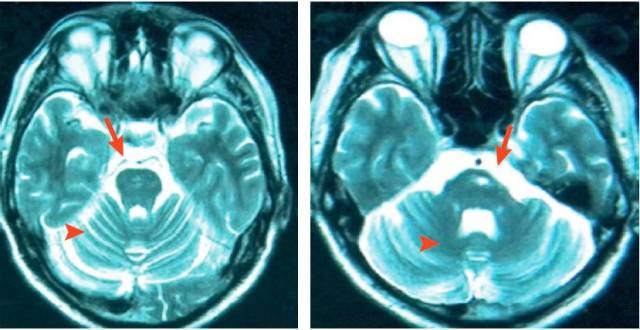

障碍疾病有关的MRI动物征丨实战读片